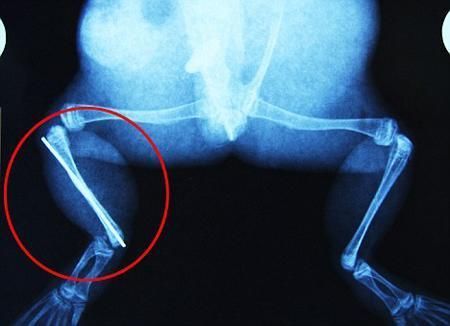

布魯萊的主人,居住在南非約翰內斯堡附近的62歲的安妮·米恩斯說:“我對這只青蛙如此關心,人們一定認為我瘋了,但是我無法眼睜睜看著它那么痛苦。青蛙因其靈活的腿腳而著稱,一想到布魯萊的腿里要留下一個薄金屬片,我就感到心痛。然而我知道,如果不進行手術,布魯萊以后就沒辦法動彈了。因此我匆匆趕到獸醫那里,央求他給這只可憐的青蛙動手術。這位獸醫整天救助小貓小狗,他很難理解為什么我這么擔心一只青蛙,但是最終他還是答應了給布魯萊做手術。手術后是幾個小時的焦急等待,我們希望它能快快蘇醒過來。不過現在它的傷口已經愈合,又能在花園里跳來跳去了。X光照射顯示,它會恢復的跟以前一樣!

野生生物專家安妮經常為學校寫教材,她認為這是人類第一次通過手術給一只青蛙接斷腿。在手術開始階段,獸醫把少量給狗用的麻醉藥注入到這只青蛙體內,讓它失去知覺。然后他在布魯萊的斷腿上切開一個小口,把一根小鋼針植入腿里。最后獸醫給它縫了9針,把切口縫合在一起。僅僅幾周后,布魯萊就能在安妮家附近活動了。這只青蛙大約已有25歲,主要以嚙齒動物、蛇和其他青蛙為食。布魯萊所屬的牛蛙種群正在不斷減小,目前只能在非洲南部的濕地里才能看到這種青蛙。

安妮有2個孩子,她已經從事20多年兩棲動物保護工作。她認為鄰居家的狗狗在把布魯萊從地下刨出來的時候,它正在地下冬眠、她說:“世界上只有這個地區能看到這種牛蛙,這種青蛙現在變得越來越稀少。因為我從事野生生物保護工作,因此認識很多兩棲動物專家,但是以前他們誰也沒見過這種事情。看到布魯萊越來越健康我非常開心。現在還需要一段時間,它的金屬腿和它的骨骼才能融為一體,那時布魯萊會跟以前一樣健康。我們認為這個過程需要幾周時間,但是一旦它完全康復,我希望把它放歸大自然,讓它重新回到它最鐘愛的濕地里!